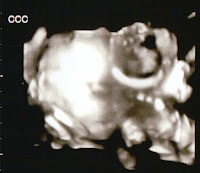

Lennon (CCC) and Coeur d'Lane's (AAA) cute faces! Can you see Coeur d'Lane's foot? Next appointment is one week from tomorrow!

Love is all you need. John Lennon Twenty four weeks and two days. Today's visit with Dr. T went very well. He took a look at the girl's hearts and they look perfect. He looked carefully for any signs of a problem from the surgery and there are none, thank God. Coeur d'Lane weighs 1 pound 7 ounces and Lennon weighs 1 pound 2 ounces (Lennon finally slowed down enough for a lovely 3D picture!). They are about 12 inches long now. During this time cells in the lungs begin to develop something called surfactant which will help air sacs in the lungs hold oxygen when they are born. As a precaution, in the event of premature delivery, Dr. T is recommending steroids which help this process. Actually, he doesn't see any indication of preterm delivery and is hopeful that Brooke will carry them a couple of more months. She's doing so well that he wants to see her back in two weeks. I am very proud of Brooke and Chris. This has been a very stressful last two and half m...